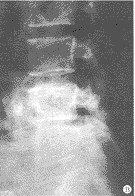

图2 1位33岁患者手术前、后X线照片

Fig 2 X-ray image of pre-operation and post-operation of a 33-years-old patient

A 33-year-old male, complained of lumbar pain and bilateral lower extremity pain caused by post-operative lumbar instability after a previous lumbar lamiectomy (spondylolisthesis of L5~S1) and degeneration of L4~5)。 Two segmental PLIF with single BAK additional with Steffee interfixiation was performed. A: Pre-operative post-anterior image; B: Post-operative anter-posterior; C: Lateral image

本组随访时间平均12.5个月(6~18个月),除1例影像学显示BAK融合器周围存在透明带, 判定为融合失败外,余皆达到临床融合(图1,2)。患者主观自我评定,12例满意,6例基本满意,2例认为可以。